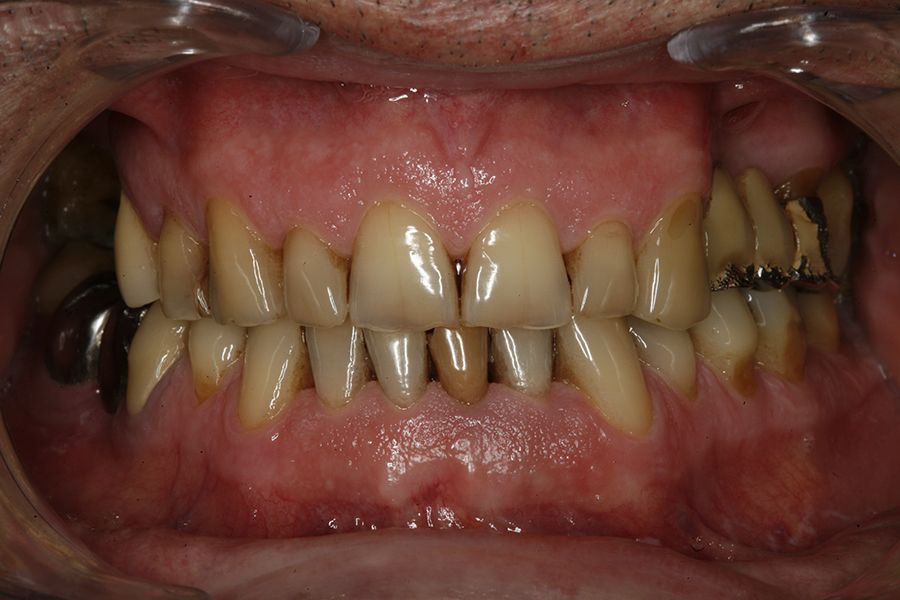

Material and method: We retrospectively recruited patients who attended our dental clinic with problems in different implant rehabilitations of an eminently mechanical nature (fracture of ceramics, prostheses, or components as well as implants) who underwent respiratory polygraphy to reveal the possible presence of OSA. In those cases where this disorder was found to be present, we selected patients with moderate-severe OSA (apnea- hypopnea index (AHI) ≥ 20) to analyze the different adverse events that occurred according to the severity of the sleep disorder recorded.

Results: Twenty-two patients who met the previously established inclusion criteria were recruited. Adverse events were identified in all patients in their implant restorations, these complications being fracture of the prosthesis ceramic (63.6%), structural fracture of the prosthesis in 18.2% of the cases (structure itself or resin coating in hybrids) and fractures or cracks in the implants in 18.2% of the cases. The mean AHI (apnea-hypopnea index) of all patients was 33.29 (+/- 18.90; range 20-110). If we analyze the presence of adverse events in the prostheses according to the AHI, we find that most adverse events are concentrated in the higher AHI ranges. A therapeutic approach with CPAP (continuous pressurized airway oxygen delivery device) combined with a mandibular advancement device (DIA) was used in two patients, the rest only DIA. With treatment completed, patients went from a mean AHI of 33.29 (+/- 18.90) to a mean of 17.38 (+-10.37), these differences being statistically significant (p<0.001).

sleep disorders such as OSA and oral pathology, for example bruxism or fractures, of various rehabilitations, both on teeth and on implants, is widely documented today. This association has been demonstrated in several epidemiological studies over the years3-7, with our research group highlighting that the presence of dental wear in patients should prompt a thorough sleep analysis, as the degree of dental wear is directly related to OSA via the AHI (apnoea-hypopnoea index)9-11. This relationship is directly proportional, and it is confirmed that patients with more severe wear also exhibit a higher AHI, which is likewise associated with an increased incidence of fractures in enamel, dental roots, and prostheses. Mechanical events may,

in some cases, also affect implants, resulting in bone defects due to overload, and in extreme cases, leading to fracture of the implant itself.12-14. In the following clinical case series, we sought to retrospectively collect a group of patients who experienced adverse events in implant-supported prostheses associated with mechanical overload (fractures, loosening), to whom a subsequent polygraphic sleep study was performed, identifying those in whom these events could be related to the presence of OSA. The most severe cases identified (AHI ≥ 20) were analysed to obtain data correlating both events (OSA and mechanical complications).